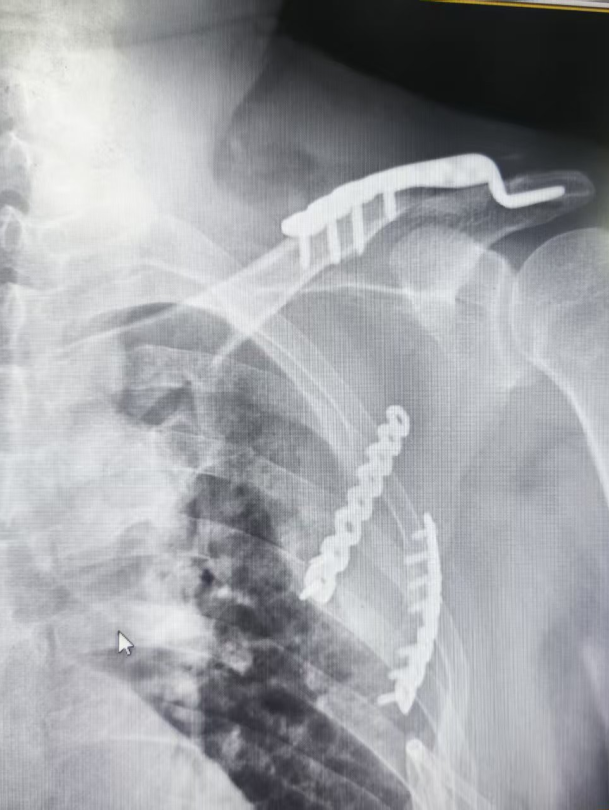

患者因严重外伤入院,被诊断为锁骨骨折、肋骨骨折以及胫骨平台骨折。

手术当日,骨科与胸外科团队紧密配合,凭借精湛的医术和丰富的经验,克服了手术中的重重困难。在麻醉科的全力保障下,手术顺利进行,成功为患者完成了锁骨、肋骨及胫骨平台骨折内固定手术。此次手术的成功,充分展示了医院多学科协作的强大实力和救治复杂病例的高超水平。